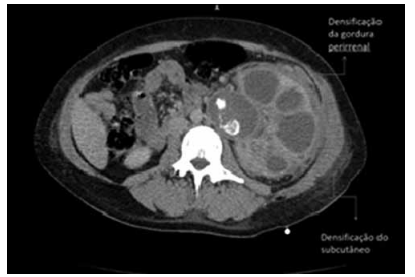

Mulher de 58 anos apresenta-se com dor no flanco, febre e mal-estar prolongado. Ela tem um histórico de infecções recorrentes do trato urinário e cálculos renais. Exames de urina revelam piúria e bacteriúria. Uma tomografia computadorizada mostra uma massa renal com características de “pata de urso” e densificação da gordura perirrenal e densificação do subcutâneo.